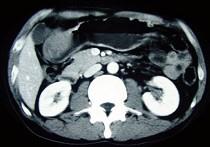

问题 女性,42岁,腹痛、黑便1周,CT扫描见胃窦部圆形块影,最佳的诊断是 ( )

选项 A.胃窦平滑肌瘤 B.胃癌 C.胃淋巴瘤 D.胃窦神经纤维瘤 E.胃内异物

答案 D